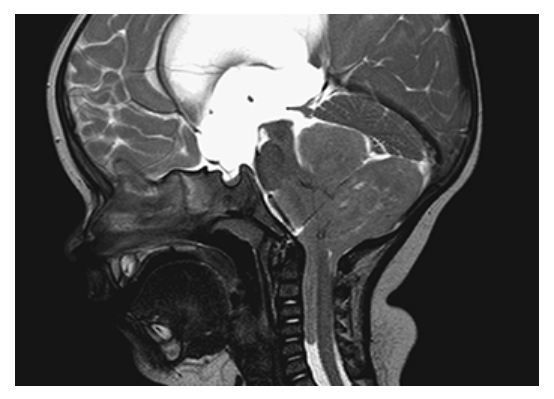

Ependymoma. Sagittal T2W image shows the large irregular mass arising from the fourth ventricle, compressing the cerebellum and herniating down the spinal canal. There is also severe hydrocephalus due to obstruction of CSF flow.